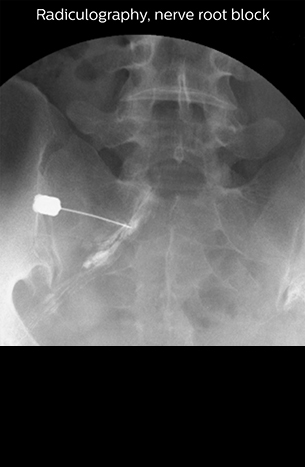

“Before NerveVIEW, diagnosis by MRI alone was sometimes difficult, unless there was a strong suspicion based on clinical symptoms,” says Shoji Yabuki, MD, DMSc, Orthopedic surgeon at Fukushima Medical University School of Medicine. “This is why we routinely perform selective lumbosacral radiculography (nerve root block) and x-ray in such cases. However, radiculography can only depict nerves as far as the contrast agent reaches. When a nerve is distorted by compression, the contrast agent will not pass through this compressed area, preventing us from evaluating the full nerve compression.”

“NerveVIEW can clearly show nerve courses and presence of nerve compression. However, when multiple abnormalities are seen, it can still be hard to determine which nerve is causing the symptoms,” says Dr. Yabuki. “In our experience so far, we see abnormal findings on NerveVIEW in about 70% of elderly patients. As the pain is usually caused by only one nerve, we thus need to find the exact corresponding nerve.” “With a nerve root block, the patient's pain is improved by infiltration of local anesthesia directly around the nerve root considered to be responsible. Knowing such nerve root block findings prior to image interpretation, helps to easily recognize abnormal findings on NerveVIEW as well. In other words, without a priori knowledge, based on symptoms and/or nerve root block findings, we must be aware of the possibility of overdiagnosis.”